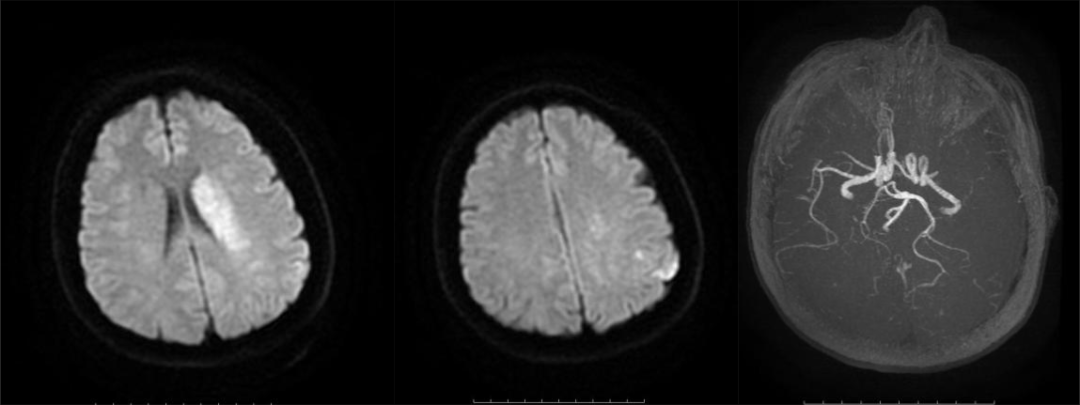

病历二:患者,48岁女性。因突发意识不清、右侧肢体无力及言语功能障碍4小时入院。经急诊磁共振成像(MR)检查诊断为急性脑梗死。

手术团队采用Solitaire取栓支架及负压抽吸成功取栓,恢复血管通畅。

左侧大脑中动脉发出颞前动脉后远端闭塞,左侧大脑中动脉开通,取出血栓。

术后患者恢复情况良好,痊愈后顺利出院。